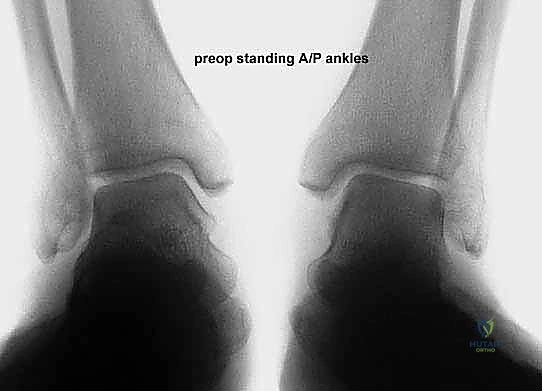

* الأشعة السينية (X-rays) مع تحمل الوزن: ضرورية لتقييم درجة انهيار القوس وزوايا العظام (مثل زاوية تالونافيكولار Meary's Angle).